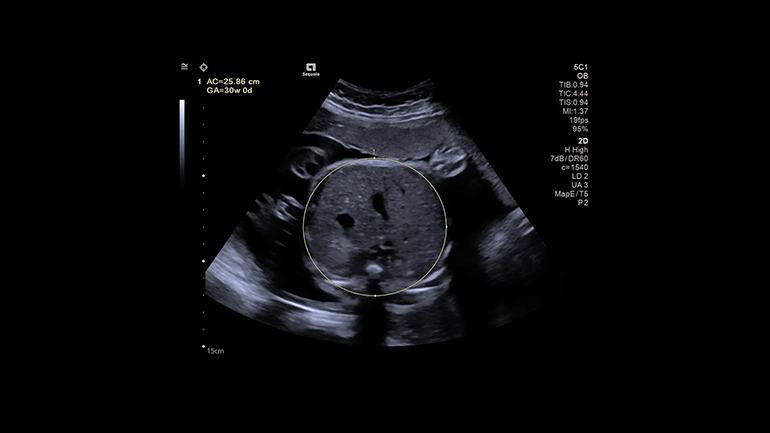

eSieOB​

Измерение eSie OB — усовершенствованный диагностический инструмент, который позволяет сэкономить до 75% нажатий на клавиши при стандартных измерениях показателей развития плода. Это улучшает рабочий процесс и повышает согласованность и воспроизводимость результатов биометрии плода.